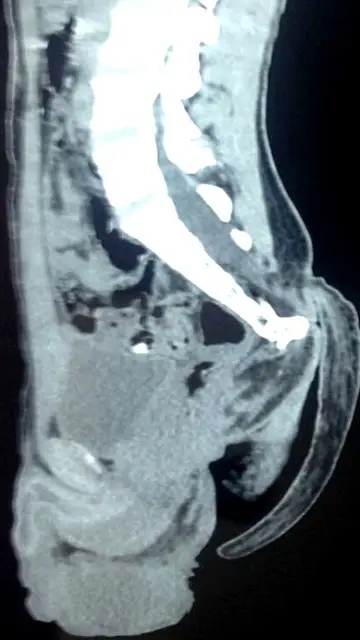

Finalmente un equipo de seis médicos eliminó con éxito la malformación en una operación de más de una hora. El doctor Pramod Giri, el jefe del departamento de neurocirugía, fue el encargado de realizar la operación y advirtió que se trata de un caso "extremadamente raro" y aseguró no haber visto "nunca" una anomalía como esa.

"La cirugía no tuvo complicaciones, pero ya que implica una cierta parte de la médula espinal había que tener cuidado. Afortunadamente, no había hueso o tejido muscular en su cola, por lo que la extirpación se realizó con éxito", aseguró Pramod Giri según el Daily Mail.